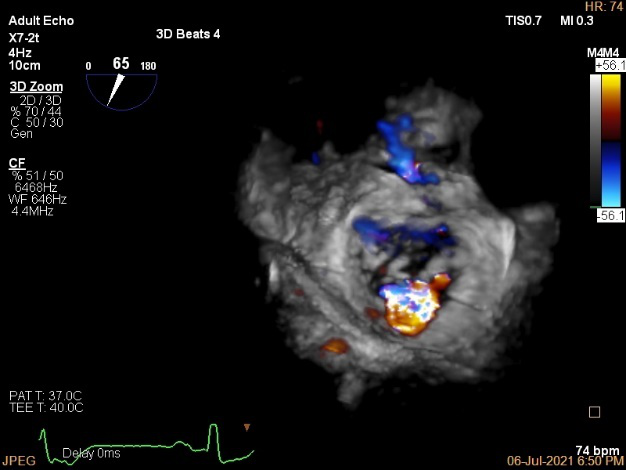

3D MV View

3D-color MV view:血流主要来源于2区近3区

Qlab软件勾画估测瓣口面积约:6.16cm²

3D视图下观察二尖瓣双孔形态

3D-color:残余少量返流